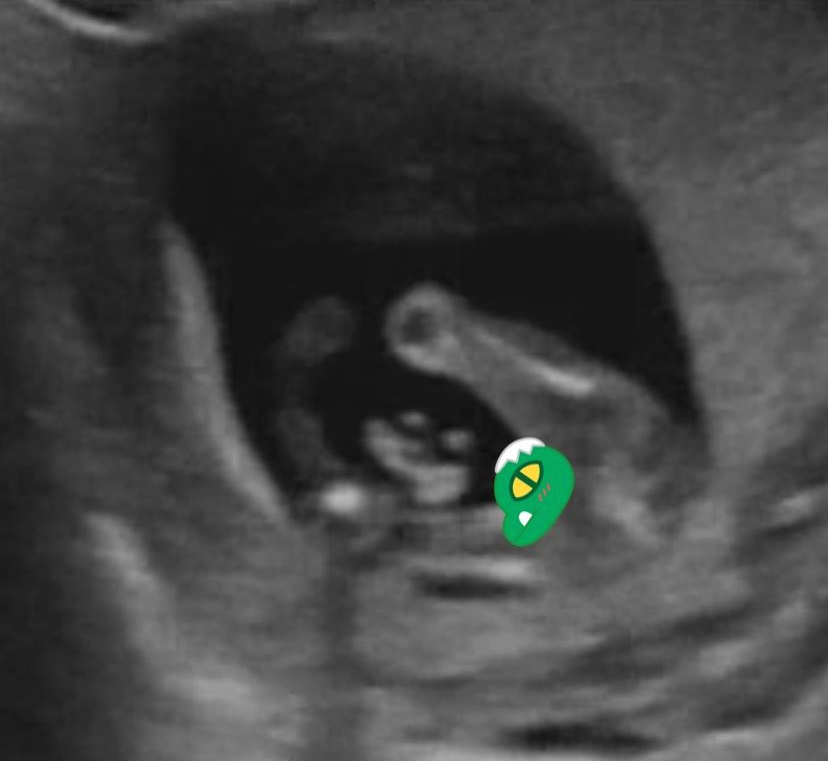

선생님, 혹시 성별은...

여전히 초음파를 이리저리 돌려보던 의사 선생님은 아직 성별을 구분할 수 있는 시기가 아니라고 말하는 순간 초음파에 누가 봐도 알 수 있는 완전한 무언가가 보였다. 나도 아내가 보내온 사진과 임신 어플의 초음파 영상에서 확인해봤는데 예쁨이의 자세는 "엄마 아빠 저 아들이에요"하며 자랑하고 있는 듯했다. 아래 초음파는 예쁨이의 엉덩이 쪽을 바라본 사진이다. 앉은 자세가 너무 사랑스럽지 아니한가.

img.png

의사 선생님은 절대 아들이라고 하지 않았고 "보이시죠?" 정도로 힌트만 주셨다. 그리고 아내는 그 힌트를 받지 않아도 아들임을 알 수 있었다. 이건 추후 성별 반전은 없을 것 같다. 명.확.하.다. 역시 우리 아들. 잘 될 잎은 떡잎부터 다르다고 했던가. 훌륭하다.